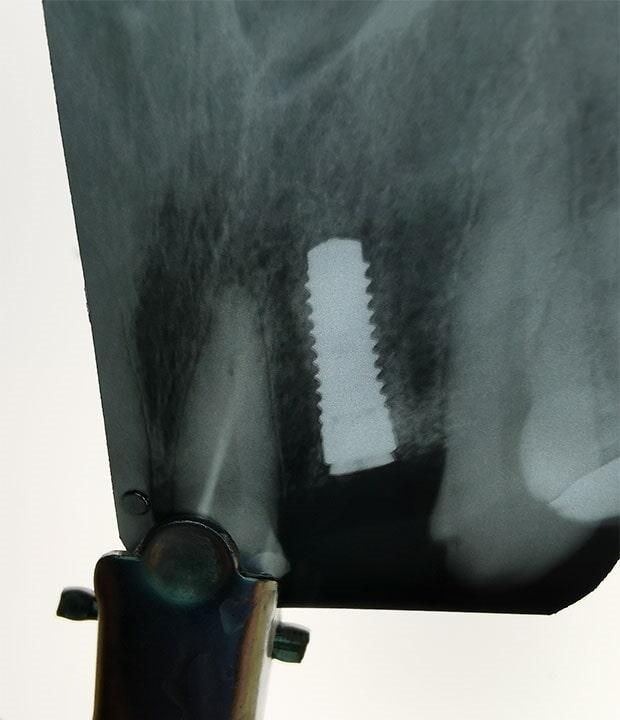

IMPLANTES

DENTALES

Antes de pensar en colocar un implante, primero deberemos realizarte una serie de estudios, así como valoración a detalle de tu cavidad oral para proponer que tratamiento es el ideal para ti.

En CIMOH contamos con equipo multidisciplinario para lograr evaluarte y decidir si eres o no candidato para este tipo de tratamientos, en caso de no serlo, también de sugeriremos diferentes opciones para tu rehabilitación.